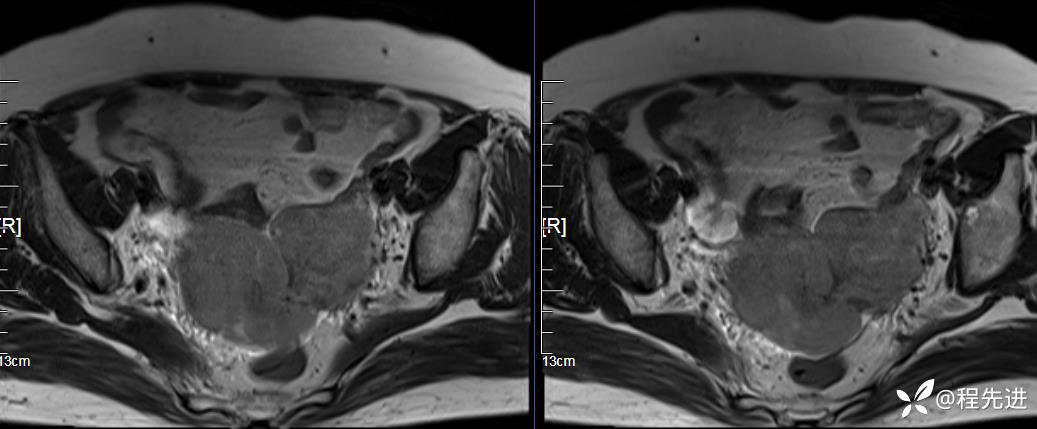

T2压脂: